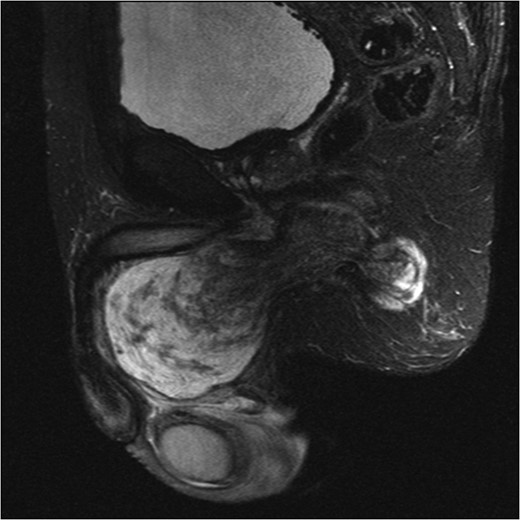

An initial ultrasound confirmed a well-defined heterogenous encapsulated solid mass with internal vascularity. An abdominopelvic MRI revealed a 5.4 cm × 7.2 cm × 15.7 cm solid-cystic well-defined lobulated mass within the perineum separate from the testicles, adjacent to the penis and extending to the right ischial fossa and the obturator internus muscle (Fig. 1). Anteriorly the mass displaced the penile urethra and bulb and the anal sphincters without direct involvement (Fig. 2). There was no locoregional or para-aortic lymphadenopathy.

MRI abdomen and pelvis T2 weighted sequence coronal view demonstrating well-defined heterogeneous mass within the perineum.